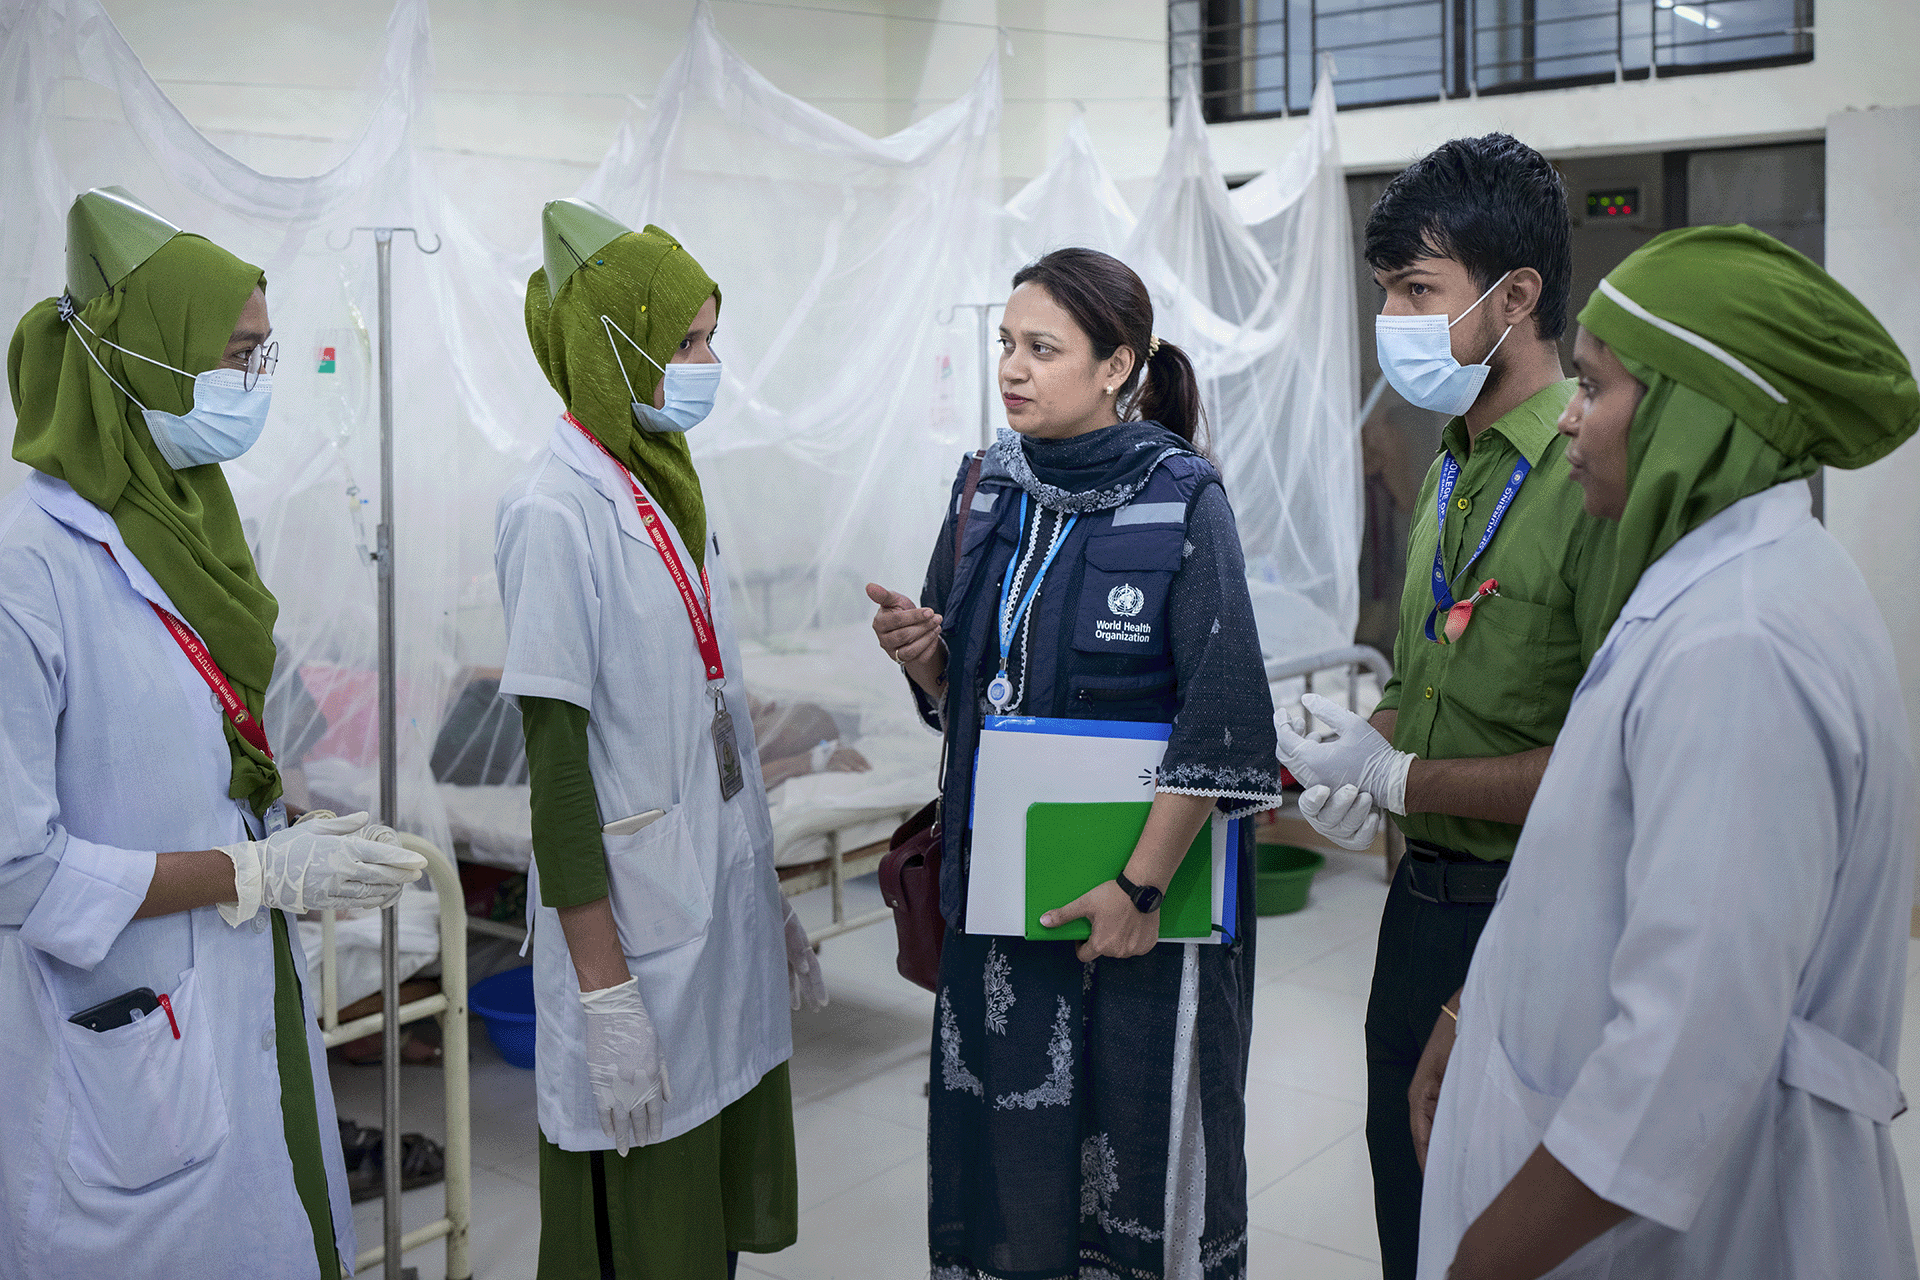

On World Neglected Tropical Disease Day 2024, WHO is calling on everybody, including leaders and communities, to unite and act to address the inequalities that drive neglected tropical diseases (NTDs) and to make bold, sustainable investments to free the estimated 1.62 billion people, in the world’s most vulnerable communities, from a vicious cycle of disease and poverty.